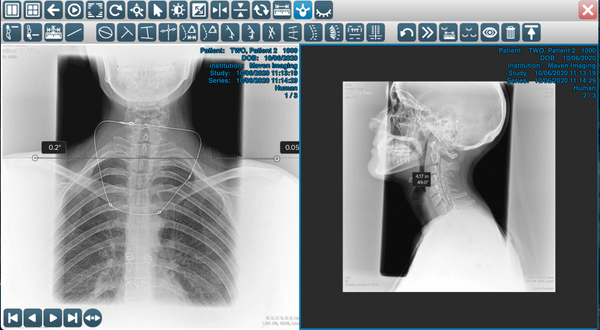

- ARA/RRA – measure Absolute Rotation Angle / Relative Rotation Angle.

- C2-C7 – measure the angle between C2 and C7 with reference value 42° displayed and display the translation between C2 and C7 in millimeters.

- C1 to Horizontal – Measure the angle between C1 to horizontal line with refrence value 29° displayed.

- C1-C7 – Measure the angle between C1 and C7 and display the translation between C2 and C7. Cervical Lordosis Upper (177 mm) – Draw the cervical curve between C1 and T2 with 177mm diameter radius.